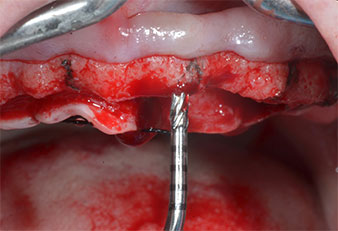

Insertos Piezomed

Fig. 4: El siguiente paso fue el aumento piloto con los insertos I2A/I2P, que se aplicaron con un movimiento rotatorio horizontal.